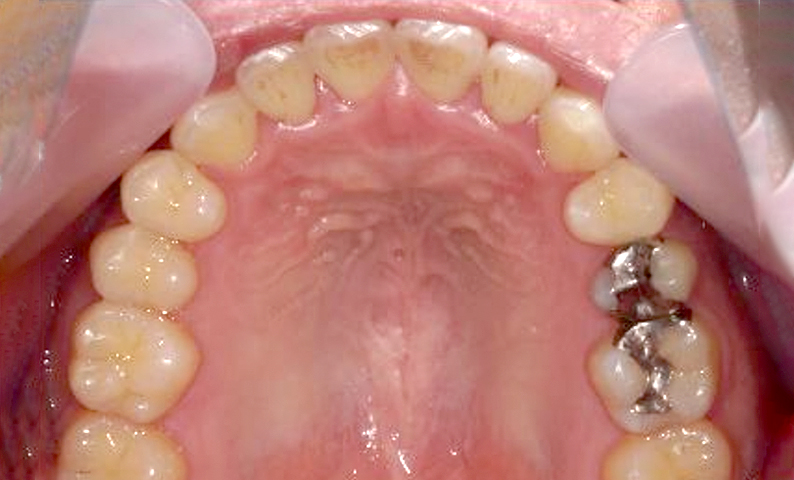

| 治療前 | 治療後 |

|---|---|

|